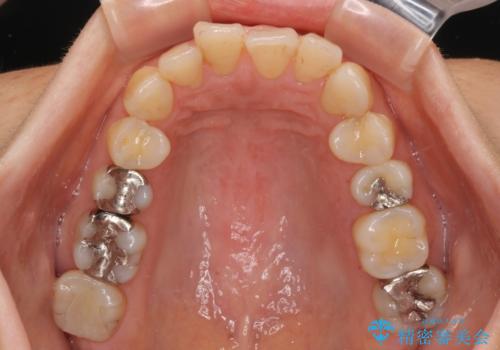

- 奥歯の銀歯をすべてゴールドにすることを希望された患者様です。

セラミックインレーによる補綴治療も提案しましたが、ご自身で強い咬合力を認識しており、歯にもインレーにもダメージの少ないゴールドインレーにて処置することとしました。

ゴールドは「白い歯」ではありませんが、銀歯の金属色とは異なり、非常にきれいな色合いが特徴です。

もちろん、適合が極めて良いという圧倒的メリットもゴールドクラウンやゴールドインレーの特徴です。